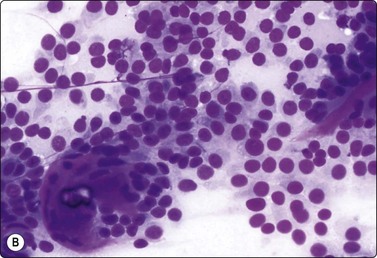

Wilms’ tumor (Figs 12.27 and 12.28)103-105

image

Fig. 12.27 Wilms’ tumor

Biphasic tumor; cohesive tubular structure and undifferentiated mesenchymal cells (MGG, HP).

Fig. 12.28 Wilms’ tumor

Small round cell tumor pattern of undifferentiated blastema (A, MGG; B, Pap, HP).

Criteria for diagnosis

Numerous undifferentiated small cells, single and in tight clusters (blastema),

Small, round or ovoid, hyperchromatic nuclei; multiple small nucleoli,

Scanty cytoplasm,

Epithelial differentiation: rosettes, tubular structures or cords (commonly present),

Mesenchymal differentiation: spindle cells (sometimes present).

Wilms’ tumor (nephroblastoma) is predominantly a tumor of childhood and is dealt with in more detail in Chapter 17. However, it can also occur in adults. Smears are usually dominated by small, undifferentiated malignant cells representing blastema. A specific diagnosis requires in addition evidence of epithelial and mesenchymal differentiation, but this may only be obvious in the better-differentiated tumors. Individual cells generally appear undifferentiated. Epithelial differentiation is suggested by microarchitectural patterns such as rosettes, tubules or cords (Fig. 12.27), which are not always present in smears. Correlation with clinical and radiological findings is important. The diagnosis may be supported by ancillary studies. The results of immunostaining are variable, depending on differentiation. Useful markers are vimentin, LMWCK, EMA and WT1. Heterogeneous cytogenetic abnormalities can be demonstrated in a proportion of tumors.